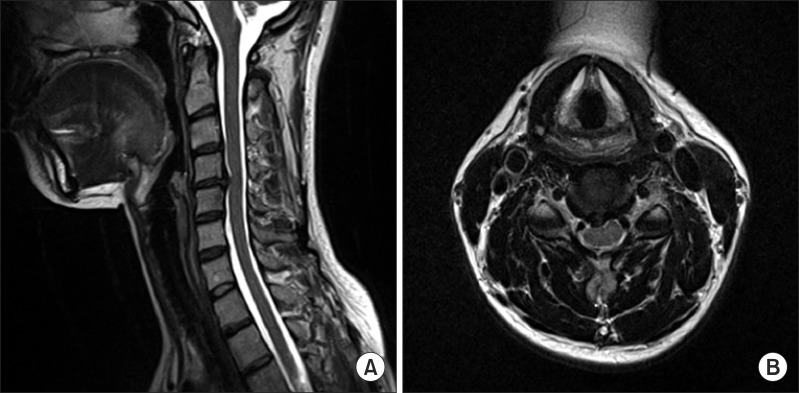

이러한 경우 정상적인 목척추 C 커브가 형성 되어있을 때보다 목이 앞으로 쭉 빠지는 거북목, 일자목이 되기쉽습니다.

거북목 일자목이 되면 정상 목 보다 머리무게의 6배 이상의 부하를 받게 됩니다. 그리고 거북목의 형태가 되면 목디스크도 쉽게 유발되고, 경추 후관절에도 문제를 일으켜 신경통의 양상도 띠게됩니다. 그러면 만성적으로 목어깨에 담이오는 증상이 생기게 됩니다.